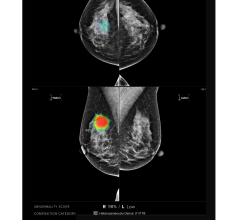

Image courtesy of iCAD

Three-D mammography is also commonly called digital breast tomosynthesis, or DBT. The technology combines low-dose X-rays with software that creates a 3-D image of the breast. Compared to 2-D mammography, DBT may make it easier for radiologists to detect an abnormality. Yet DBT has not been widely endorsed for routine breast cancer screening. Organizations like the U.S. Preventive Services Task Force and the American Cancer Society, which provide guidance to clinicians about cancer screening, have not made recommendations for or against the routine use of DBT.